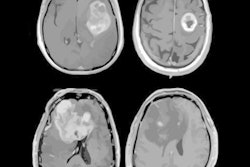

A dose-intensification protocol used with intensity-modulated radiation therapy (IMRT) failed to improve overall survival compared with standard radiation therapy for glioblastoma in a study reported on October 26 at the American Society for Radiation Oncology (ASTRO) meeting.

The randomized NRG-BN001 study compared dose-escalated photon IMRT against standard-dose radiation therapy, both with the drug temozolomide, in 229 patients newly diagnosed with glioblastoma. The toxicity profile for dose-intensified IMRT was similar to standard dosing, but efficacy fell short as it failed to significantly improve overall survival, researchers reported at the meeting.